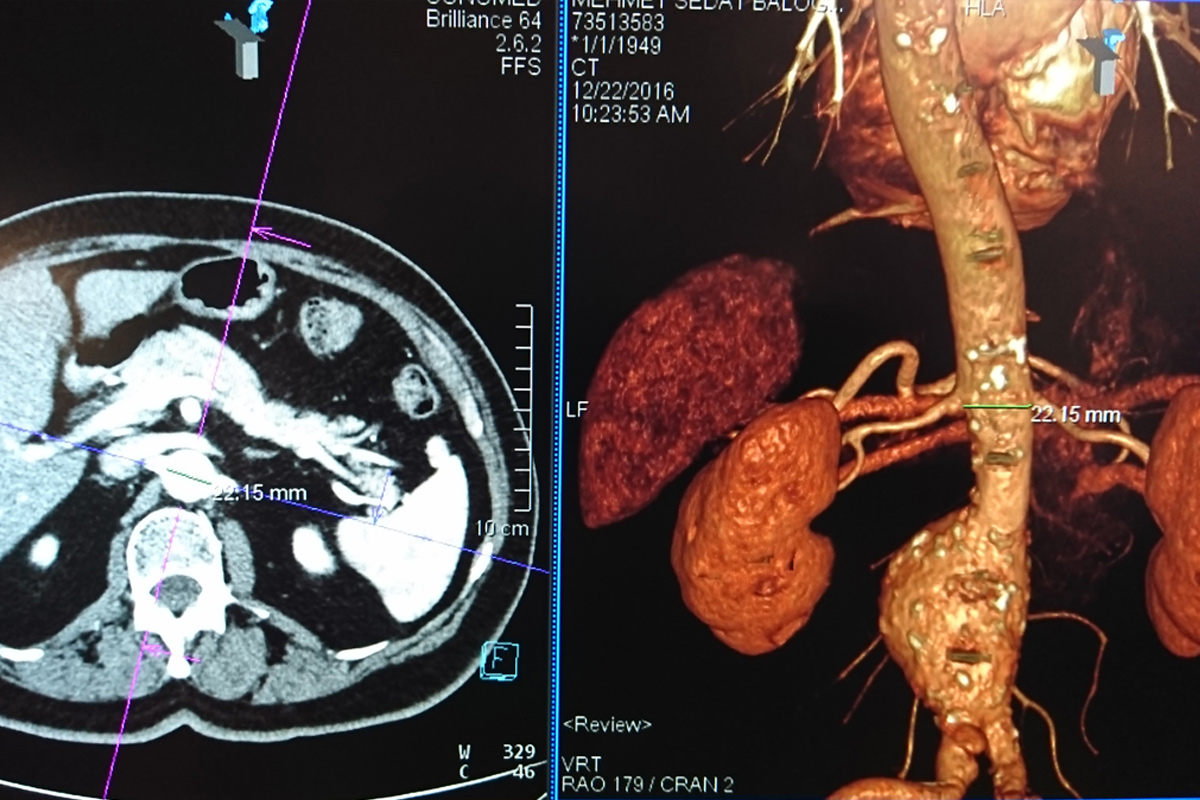

Abdominal aort anevrizmasının tanısı ultrasonografi, mayetik rezonans ve bilgisayarlı tomografi anjiografi ile konabilir. Ancak tedavi yöntemini seçmede ve hastalığın anatomisi ile ilgili detayları saptamada en yararlı yöntem BT anjiografidir.

Bilgisayarlı tomografi ile abdominal aortun anatomik özellikleri 3 boyutlu olarak değerlendirildikten sonra her hasta için ayrı ve özel stent greftler hazırlanır. Anjiografi salonunda öncelikle her iki kasık damarı cerrahi olarak hazırlanır ve bu damarlar aracılığı ile yapılan işlem ile hastaya özel hazırlanan stent greftler anevrizmatik damar bölgelerini kapatacak şekilde damar içine yerleştirilir. Daha sonra kasık bölgesindeki damarla tamir edilerek kesiler kapatılır ve işlem sonlandırılır.